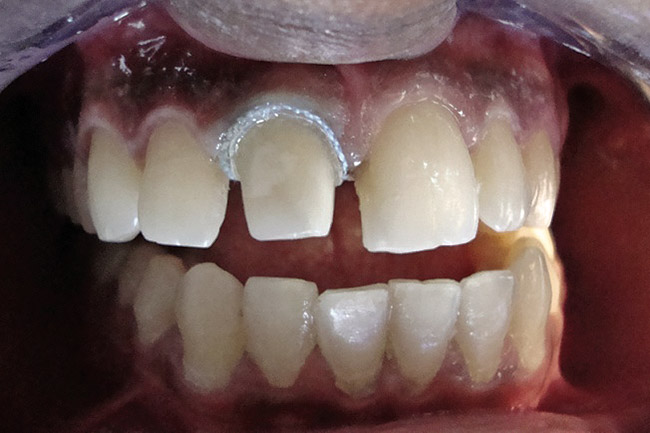

Figure 3  Placement of rubber dam with application of cervical clamp on central incisor for extra retraction.

Figure 3